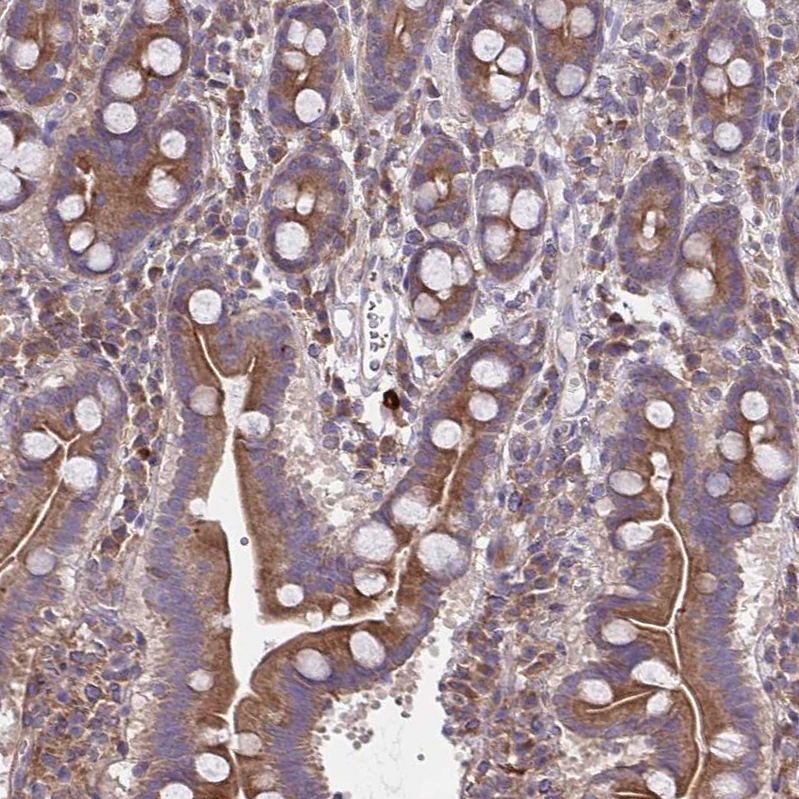

Immunohistochemical staining of human kidney shows strong cytoplasmic positivity in cells in tubules.